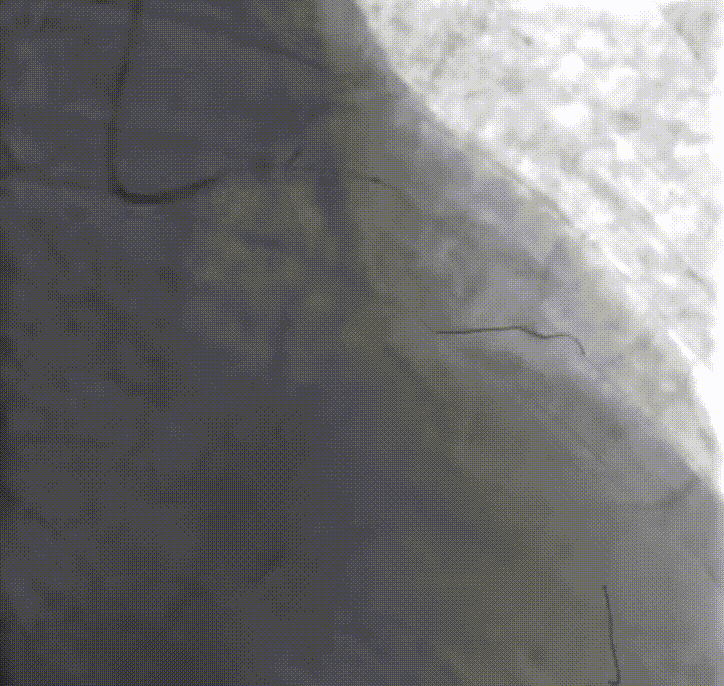

首先右冠远段至近段串联植入2.75*28mm、3.0*23mm药物支架两枚,复查造影显示管腔狭窄解除,TIMI血流3级。

于LM-LAD中段由远及近串联植入3.0*28mm、3.0*23mm药物支架,两枚支架重叠3mm,并使用3.0*12mm、3.5*12mm非顺应性球囊支架内后扩张。复查IVUS可见支架膨胀完全,贴壁良好,LM中段最小支架内面积(MSA)7.09mm²,LAD近段 MSA 6.39mm²,中段MSA 6.43mm²,远段MSA 5.20mm²。复查造影未见明显残余狭窄,TIMI血流3级。